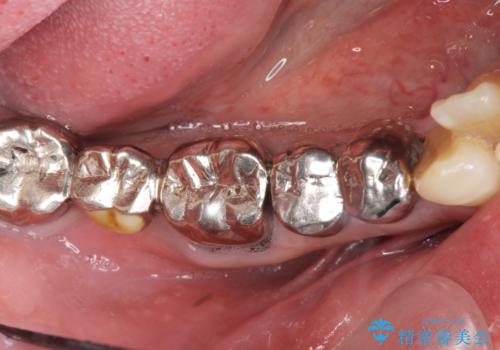

多数の銀歯と虫歯、セラミック・インプラント治療

- 銀歯だらけの口腔内を全てきっちり治療したい、と希望され来院されました。

検査の結果、残すことの難しい歯をインプラントに置き換え、残すことのできる歯は虫歯の徹底的な除去後にセラミック治療を行っていくこととしました。